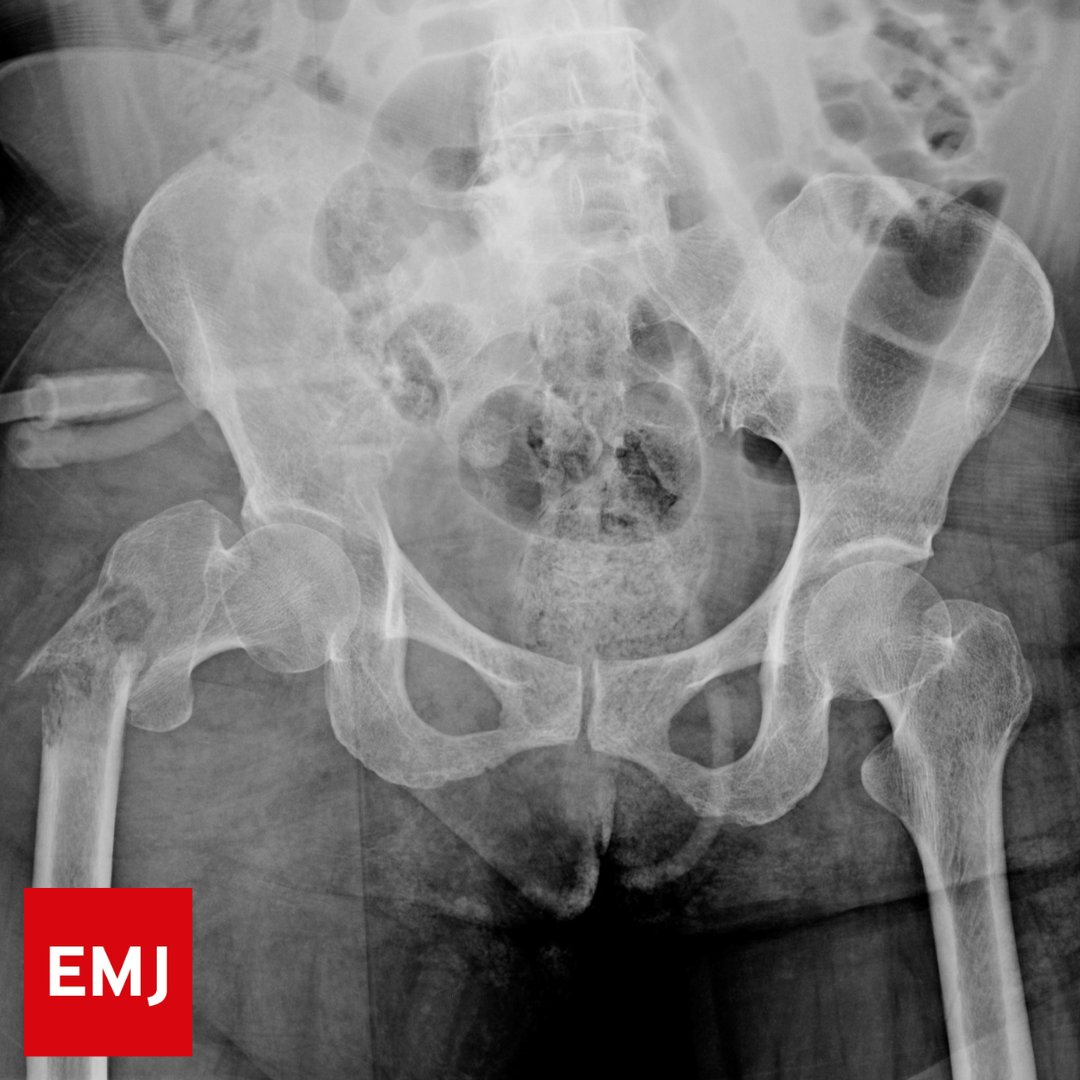

#November2024 Delayed admission of patients with hip fracture from the emergency department is associated with an increased mortality risk and increased length of hospital stay Delayed disposition was independently associated with an increased mortality risk at 90 days and at

Delayed admission of patients with hip fracture from the emergency department is associated with an increased mortality risk and increased length of hospital stay

Delayed disposition was independently associated with an increased mortality risk at 90 days and at